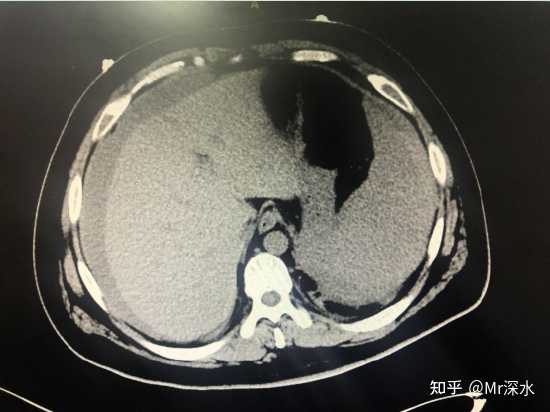

CT�µĸ�ǻ��Ѫ ֮���Խ�����ҽ�绹��Ѱ����ν�ġ����硱����������Ѫ��������֤���ż��о��������ֵ���Щ���������� �����ַ�����˼�ġ�������ҽ�ż��ż����� �Ҵ�ǰ���ܹ���ҽ��˿�������ľͷ�����С� ��٢����Ԥ�������� ��Ե������������Ԥ������ʯ���Ӵ����н�ʿ ����ġ�̫����������Ԥ��������� ���� �������Ϊ��ν����ҽ��������Ĵ��ڣ������Ʒ��������Ѫ�ܵĹ۵�����Ҳûʲô��˵���� ���Ѿ�����ѧ��̽�ֵķ�Χ�����ڡ��⽨���š��ķ����� ����ҽ�Ͷ���תת������֤�� |